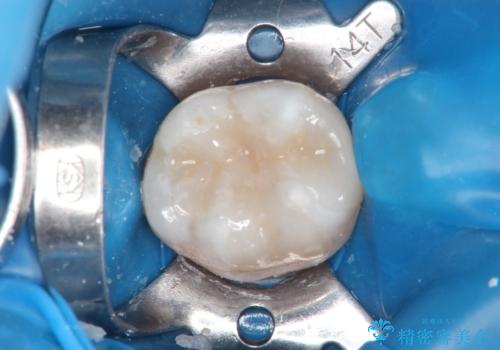

メタルフリー セラミックインレーによる治療

- 金属の詰め物を白くしたいと来院された患者様です。

セラミックインレーによって治療を行いました。

当院でのセラミックインレーはすべてe-maxと呼ばれる高強度セラミックにて製作されます。

また、製作方法もプレスと呼ばれる方法を用いることで精度を高めています。